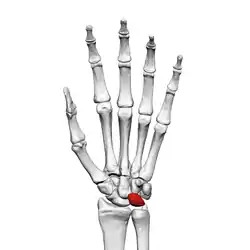

The lunate bone (semilunar bone) is a carpal bone in the human hand. It is distinguished by its deep concavity and crescentic outline. It is situated in the center of the proximal row carpal bones, which lie between the ulna and radius and the hand. The lunate carpal bone is situated between the lateral scaphoid bone and medial triquetral bone.

The lunate is a crescent-shaped carpal bone found within the hand. The lunate is found within the proximal row of carpal bones. Proximally, it abuts the radius. Laterally, it articulates with the scaphoid, medially with the triquetral, and distally with the capitate. The lunate also articulates on its distal and medial surface with the hamate bone.[1]:708[2]

Lunate bone of the left hand (shown in red). Animation.